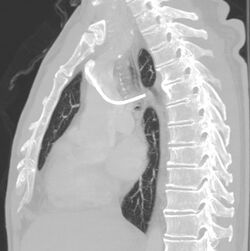

Follow-up chest X-ray after insertion of a port, with a malpositioned tip in the azygos vein.

CT scan confirming a tip in the azygos vein.